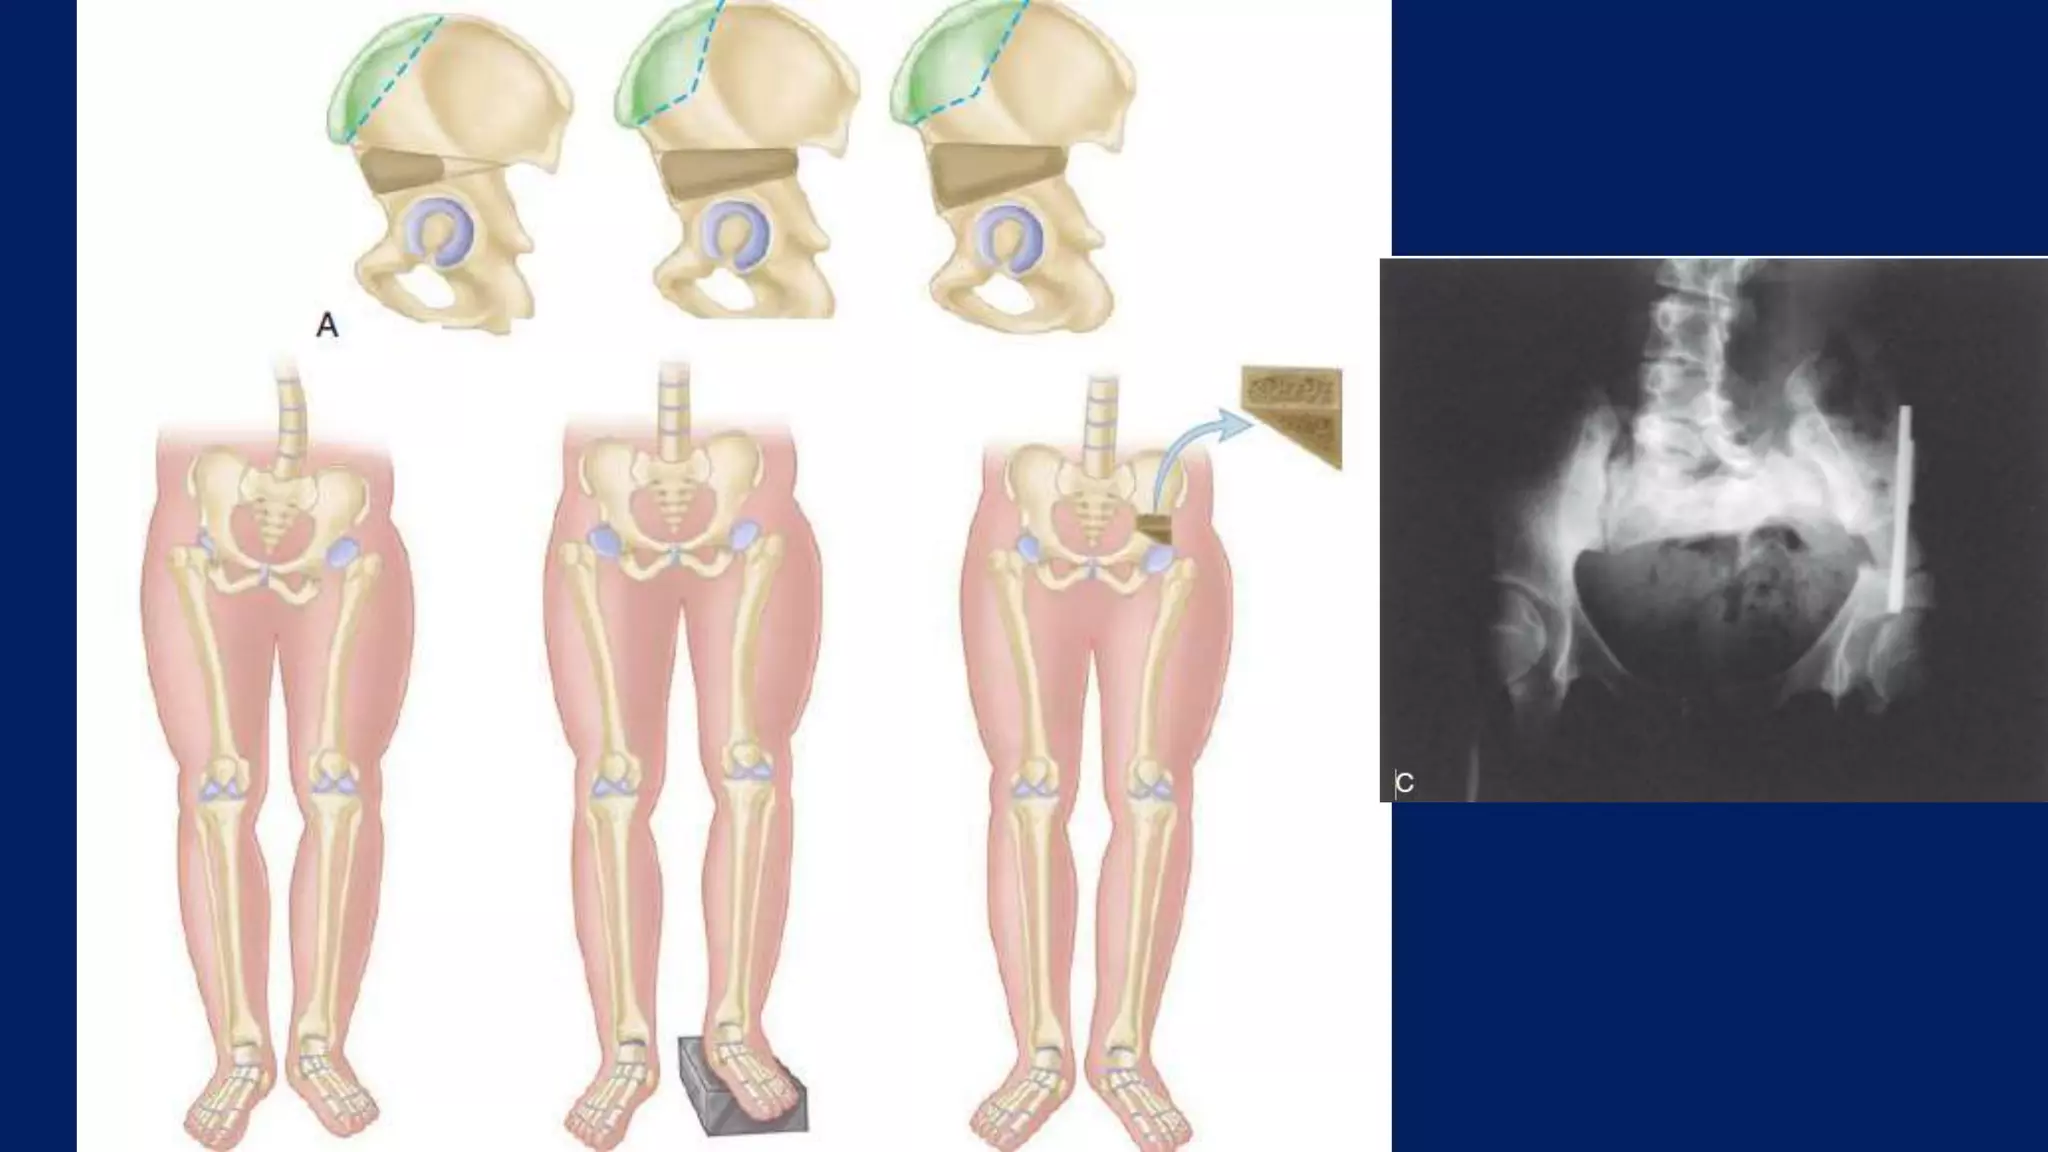

Transiliac: (MILLIS AND HALL)

• Average lengthening of 2.3 cm

Indication

• Acetabular dysplasia with femoral shortening

• Pure LLD

• Decompensated scoliosis

• Primary intrapelvic assymmetry

One stage lengthening: Transiliac:(MILLIS AND HALL) • Average lengthening of 2.3 cm Indication • Acetabular dysplasia with femoral shortening • Pure LLD • Decompensated scoliosis • Primary intrapelvic assymmetry